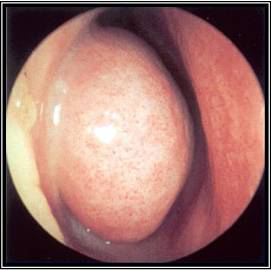

The nasal cavity should be examined for the presence of mucosal erythema or purulent discharge. Optimal exam is performed after topical decongestant spray.[18]Benninger MS, Ferguson BJ, Hadley JA, et al. Adult chronic rhinosinusitis: definitions, diagnosis, epidemiology, and pathophysiology. Otolaryngol Head Neck Surg. 2003 Sep;129(3 Suppl):S1-32. Either an otoscope or a nasal speculum and head light may be used. However, because nasal exam may be difficult or the signs nonspecific, nasal endoscopy is recommended in selected patients, including patients refractory to empiric antibiotic therapy or where there is concern for antibiotic resistance, or in immunocompromised patients.

Endoscopy can provide excellent visualization of the nasal cavity and sinus drainage paths. There are two types of endoscope: rigid and flexible. A rigid nasal endoscope has superior resolution and only requires the use of one hand. This easily allows cultures of the nasal cavity or sinus to be obtained if necessary. A flexible nasal endoscope is more comfortable for patients, but requires both hands to use. There are flexible nasal endoscopes that have a channel for collecting cultures, but these tend to be larger and more uncomfortable and they are also more difficult to reprocess. Generally, the flexible nasal endoscope is preferred in children as it is better tolerated; however, either type may be used in adults and children. Choice will depend on the practitioner's familiarity with the procedure, and most will be performed by an ear, nose, and throat specialist.

[Figure caption and citation for the preceding image starts]: Left middle meatus with healthy mucosa and non-purulent secretionsFrom the collection of Melissa Pynnonen, MD [Citation ends].

[Figure caption and citation for the preceding image starts]: Nasal endoscopy of the left nasal cavity showing a small polyp and pus in the middle meatusFrom the collection of Joseph K. Han [Citation ends].